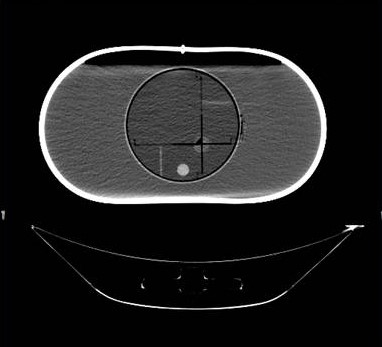

IROC Houston has developed a liver phantom. The phantom includes a liver with two targets, and 2 organs at risk. Click here for irradiation guidelines and forms for photon therapy, and click here for guidelines for proton therapy.